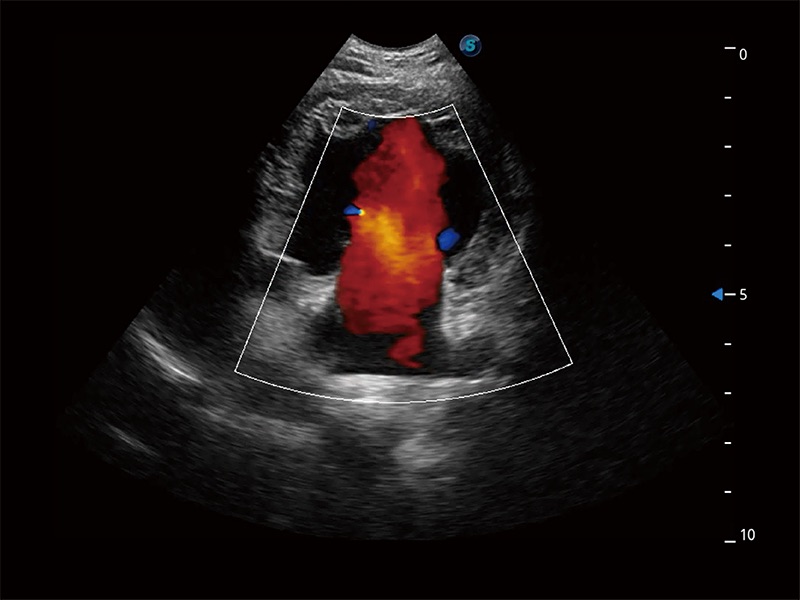

在傳統(tǒng)二維血流成像的基礎上,呈現(xiàn)血流的立體感,具有動感的生命力之美。即便是微小的血管也能輕松應對,提高了血流的視覺敏感性。

ProPet 80 配備了豐富的心臟探頭群、先進的成像技術(shù)和專業(yè)的心臟測量工具,可幫助動物醫(yī)生為不同體型和生理結(jié)構(gòu)的動物提供心臟和心肌功能的全面評估。